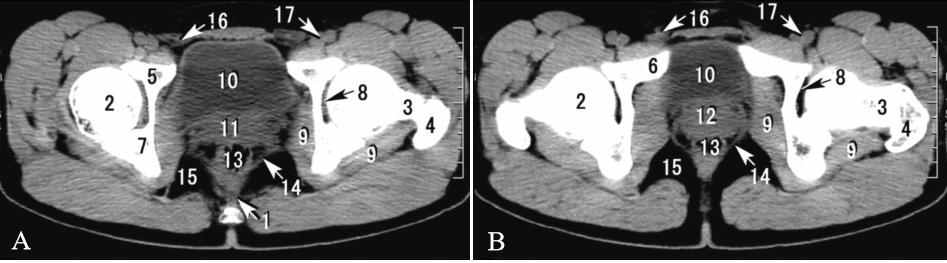

下图为经耻骨体(A)和耻骨上支(B)的横断层CT(男),请写出图中数字标注的结构